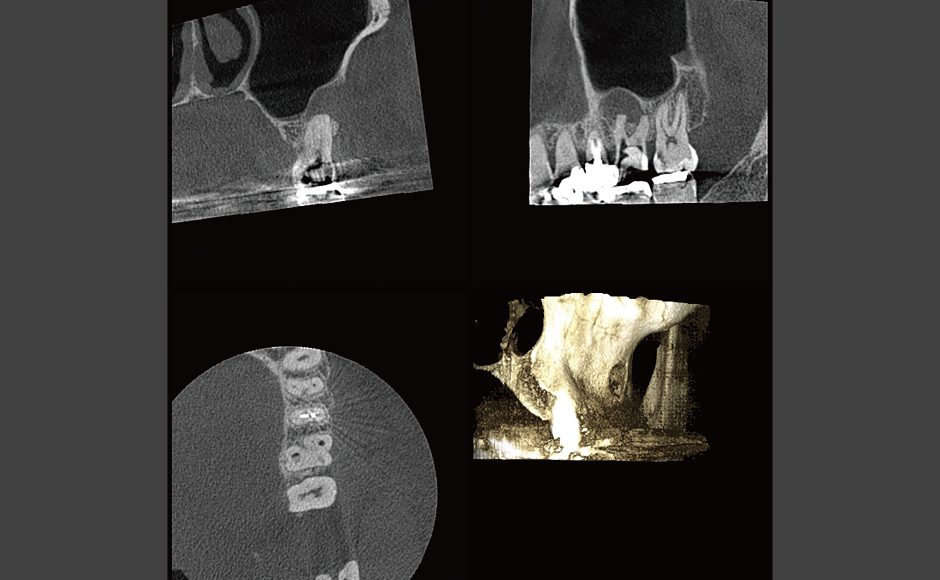

THE FRONT LINEC&C Vol.63 2024 April

レーザー療法実践応用講座

嚢胞様透過像が認められる症例に

対し、Nd:YAGレーザーを

根管内から直接アプローチした症例

医療法人社団 BTDC文京瀧田歯科医院

理事長 瀧田 稔弥 先生

瀧田先生は2022年に「医療法人社団BTDC」を設立し、理事長に就任。根管治療専門医院の「本郷瀧田歯科医院」(小林寛院長先生)を分院として開業しました。二つの歯科医院が連携して治療にあたると共に、本郷瀧田歯科医院では、根管治療の紹介や症例相談にも対応しています。

- レーザー症例1 他院より精査加療依頼

- レーザー症例2 左上奥歯が腫れて痛いとのことで急患来院。先週までは目の下まで腫れていたが、今は治ってきているとのこと。

- レーザー症例3 左上奥歯がズキズキ痛む。